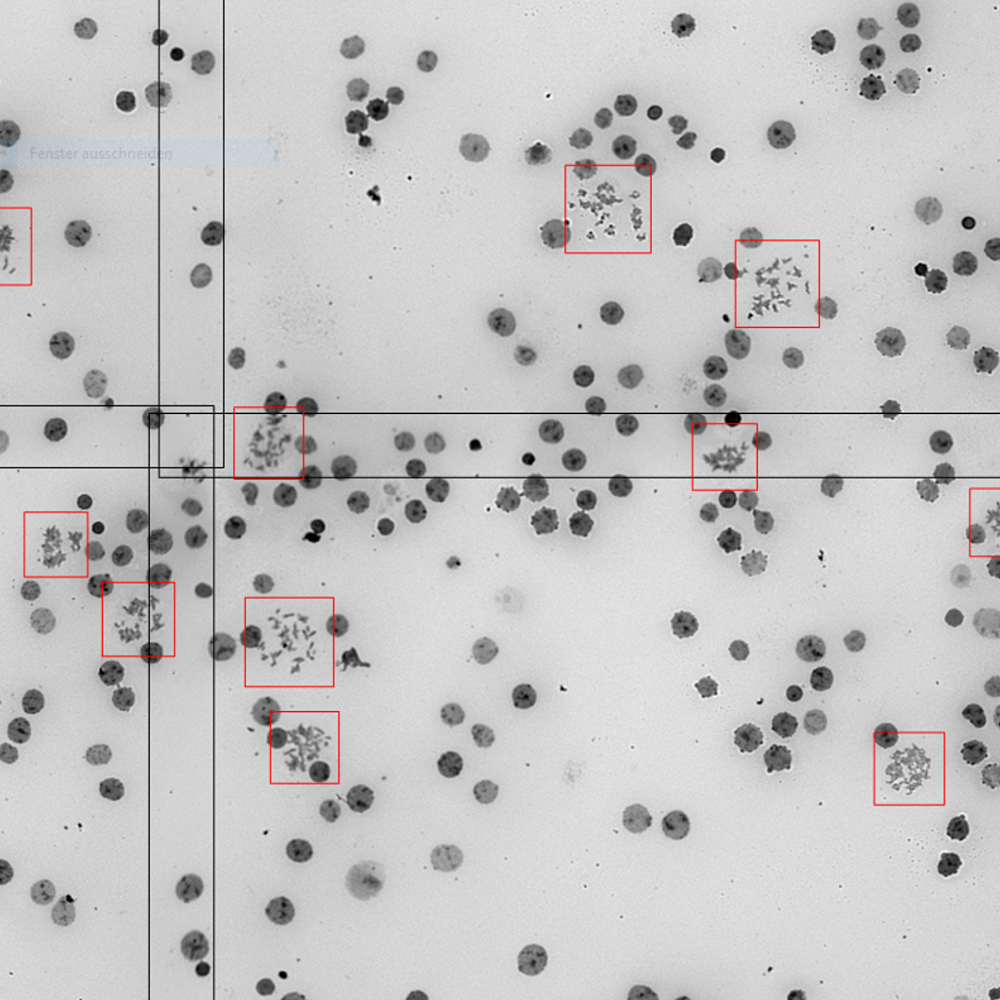

Recognized objects, e.g. metaphases, are automatically displayed in a real-time gallery during the search process. They can be easily relocated by clicking on the corresponding gallery image for detailed examination. To capture high-resolution images, metaphases can be selected either interactively or automatically, based on the user’s workflow settings. In the interactive method, the user simply selects metaphases of choice using the mouse. Alternatively, search parameters can be configured to assign user-defined quality values to the metaphases, allowing for the automatic selection of the top-rated objects. Additionally, a few randomly selected objects can also be captured. Once acquired, the images are immediately accessible to any connected workstation.

With support from MetaSystems application specialists, users can tailor their installations to include Deep Neural Networks (DNNs), an advanced form of artificial intelligence, to address challenging scenarios such as poorly prepared cells or suboptimal cell cultures. DNN functionality is provided alongside the basic software and is customized to align with individual workflows, meeting specific customer requirements. These customized DNNs are stored locally within the institution's IT infrastructure. When integrating AI into a customized workflow, users are responsible for validating the DNN as part of their workflow validation process. For example, using DNNs for metaphase detection can improve detection rates, thereby reducing the number of objects requiring capture as high-resolution images. This method has the potential to significantly accelerate result review within a user-defined workflow, ultimately shortening overall case processing time.

Once the Metafer Platform Software is installed in your lab, you can configure workflows to detect metaphases on slides automatically. Metafer offers two object detection methods. The first is based on classic machine learning algorithms, which quickly identify metaphases and display them as gallery images after the search. This method is fast and commonly used by many customers. More recently, the platform has also incorporated Deep Neural Networks (DNN), which can be trained to identify metaphases from images classified by the users. Although this method is a bit slower than the traditional algorithms, our customers report that it provides more accurate and specific results. The choice between these two methods depends on various factors, and during the customization process, our application specialists will assist you in developing the most appropriate workflow for your laboratory.